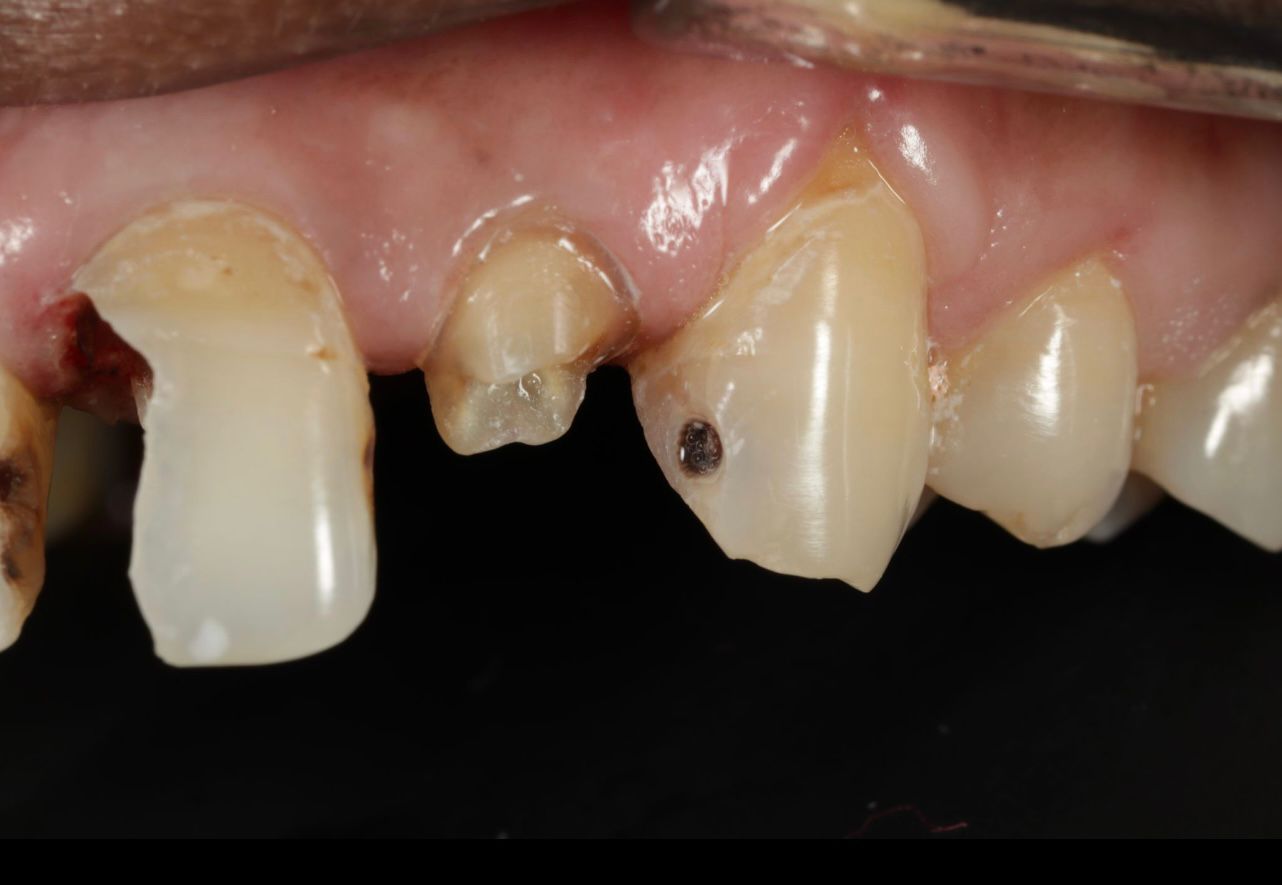

Examination revealed an intraoral sinus tract adjacent to a previously root canal-treated tooth. The tract was non-tender but expressed a small amount of pus on pressure. The existing full-coverage crown appeared intact externally, masking the underlying issue.

These findings confirmed failure of the earlier root canal, likely due to persistent infection or incomplete cleaning of the root canal system.